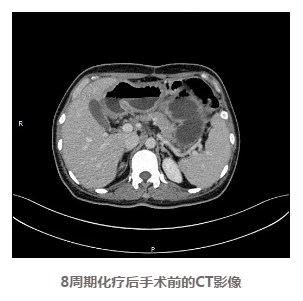

手术解决了梗阻问题,李女士的进食情况明显改善,逐步进流食、半流食、软食,直到可以少量多次进行基本正常饮食,体力状态和体重也逐渐恢复,根据方案进行了双药联合化疗,期间耐受性良好,复查CT显示肿瘤逐渐缩小。

患者的化疗取得了良好的治疗效果,通过检查评估肿瘤也已经明显缩小,此时到底是继续化疗还是选择手术治疗又成为了需要慎重选择的一个问题。为全面评估当前治疗效果,稳妥推进后续治疗,专家们再次为李女士进行了MDT(多学科会诊)